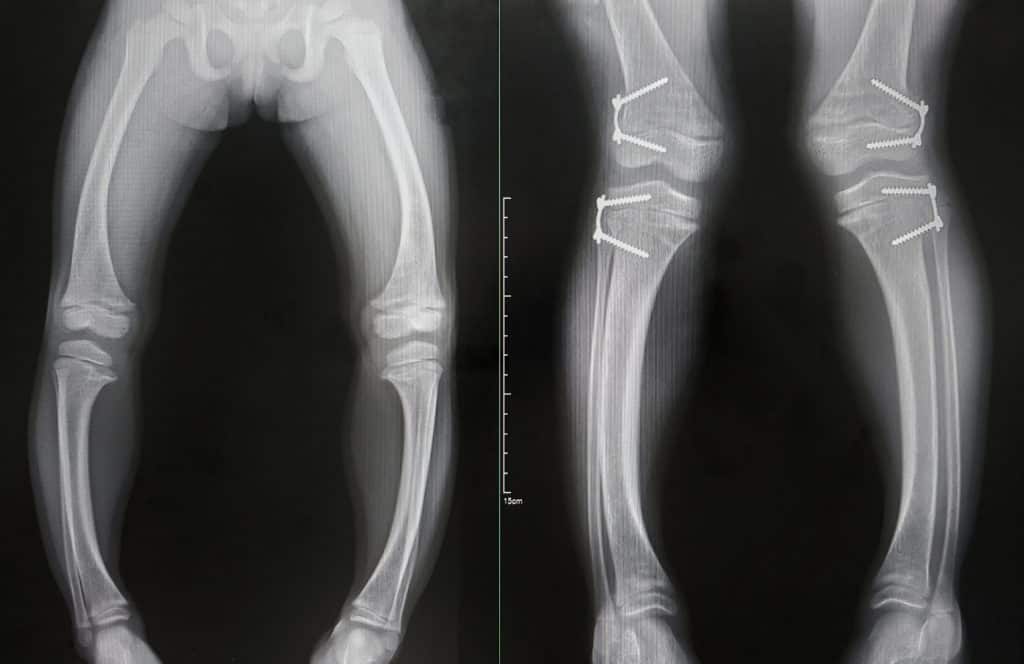

Kod rasta i razvoja navedena bolest se često manifestira i u iskrivljenim nogama koje idu u oblik "X" ili "O", drugim koštanim deformacijama u područjima ključne kosti, lubanje, čela, leđima, zubima. Djeca će tako biti nižeg rasta i imati mišićnu slabost. Kosti će biti sklone lomovima a mišići će biti više mlohavi. Rahitis kod odraslih ili osteomalacija je gubljenje čvrstoće kostiju u odrasloj dobi. Navedeno stanje dolazi kada dolazi do poremećaja mineralizacije u kostima nakon što su one narasle.

Sama dijagnoza za Rahitis se može utvrditi putem pretrage krvi i RTG pretrage koje će pokazati promjene kostiju. Liječenje rahitične djece će se odvijati dovoljnim unosom vitamina D, fosfora i kalcija. Tijekom trajanja terapije redovito će se provjeravati razine minerala i vitamina u krvi. Kod liječenja odraslih također se provodi gore navedeni plan i tretman.